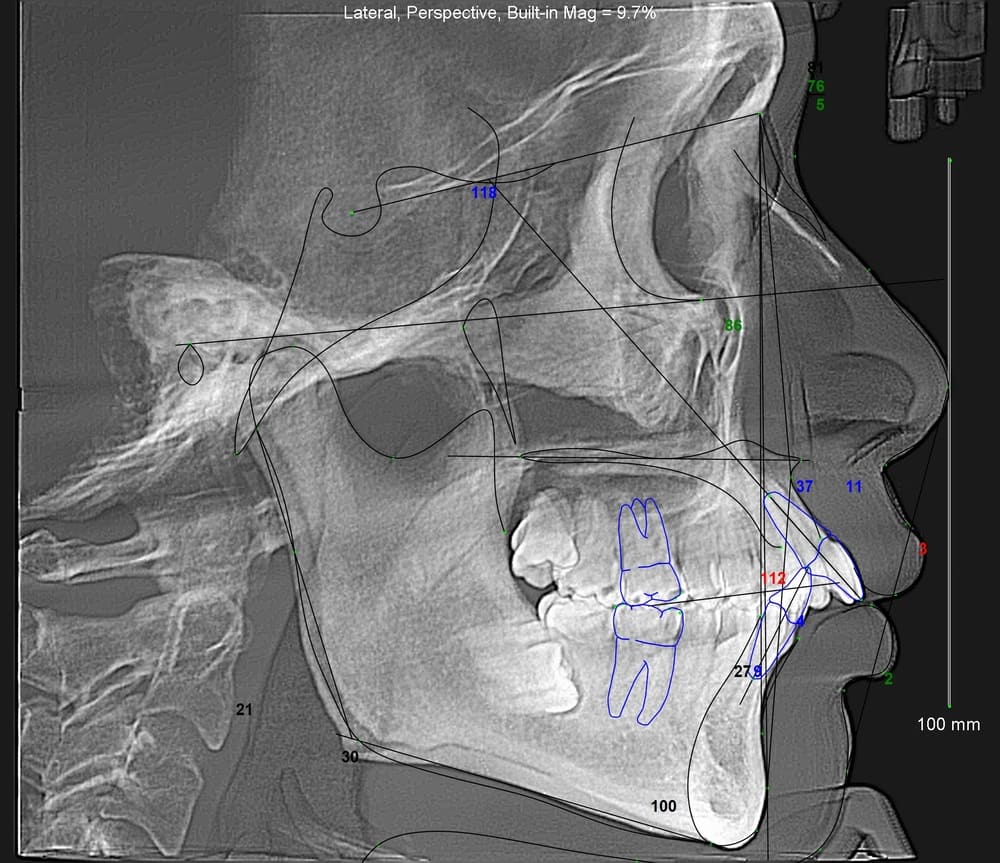

・セファロ分析による詳細な顎骨と歯の位置関係や問題点の抽出

・必要に応じて治療前後の横顔改善のシミュレーション